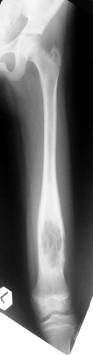

Post Op

Graft taken well

1cm shortening

of left femur

ROM : 0- 110’